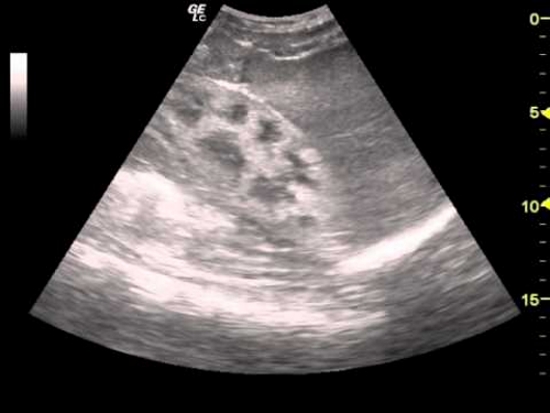

Уратный нефролитиаз обычно имеет двусторонний характер. Камни не видны на рентгеновских снимках, поэтому для диагностики используется ультразвуковое исследование. В период ремиссии изменения в составе мочи отсутствуют. При почечной колике могут появляться кровянистые включения и выход конкрементов с мочой. Длительное обострение может привести к пиелонефриту и постренальной почечной недостаточности.

| Изменения на УЗИ почек (увеличение, снижение эхогенности) | Все стадии | Лечение основного заболевания |

Подагрическая нефропатия диагностируется с помощью лабораторных и инструментальных исследований. Общий анализ крови показывает повышенное содержание мочевой кислоты. В синовиальной жидкости можно обнаружить кристаллические соли. Для окончательной диагностики необходимо исключить другие патологии, проявляющиеся гиперурикозурией:

Нефропатия может проявляться различными симптомами, такими как отеки, повышенное артериальное давление, изменения в мочеиспускании (например, частота, цвет или запах мочи), а также общая усталость и слабость. Для точной диагностики важно обратиться к врачу, который проведет анализы крови и мочи, а также может назначить ультразвуковое исследование почек.